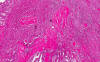

Nuclear features: These high-magnification photos illustrate the characteristic nuclear features of papillary carcinoma of thyroid which include enlarged nuclei with pale "watery" nucleoplasm, pseudonuclear inclusion (arrow in the left panel) and nuclear grooves arrow in the right panel). Overlapping of the nuclei is also a characteristic feature.